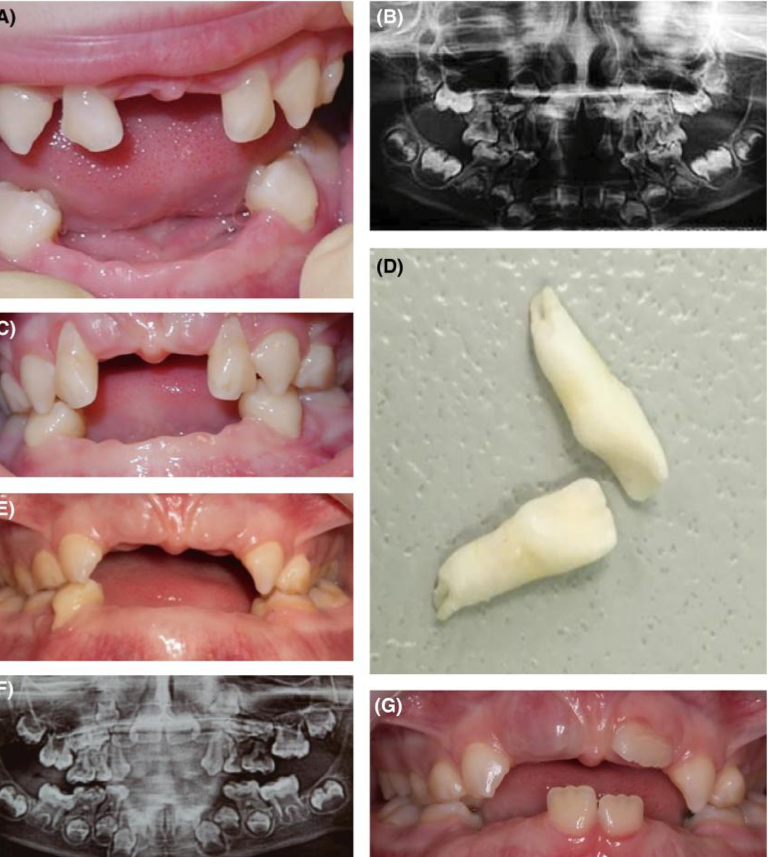

hypophosphatasia

hypophosphatasia - premature exfoliation of primary teeth w little or no root resorption

HPP

treatment plans and considerations for hpp pts

hpp presentation